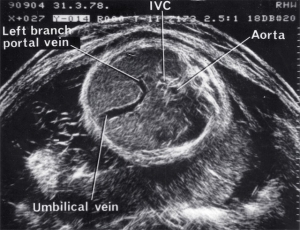

- Fetal anatomy

| 1980 | Monitoring of fetal umbilical venous blood flow in normal and complicated pregnancies |

- First umbilical vein flow measurement (1977)